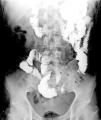

A previously healthy 48-year-old man came to the emergency service presenting with diffuse abdominal pain of three-month progression, associated with periods of diarrhea, bloating, and weight loss of approximately 10kg. Upon admission, his vital signs were within normal parameters and abdominal examination showed no peritoneal irritation, masses, or visceromegaly. A calprotectin stool test reported fecal calprotectin of 2,351μg/g (reference value:<50μg/g) and a lower gastrointestinal barium x-ray revealed filiform contrast medium passage at the level of the ileum (string sign) (Fig. 1). During colonoscopy, active ulcerative ileitis was observed, with a polyp at the mouth of the ileocecal valve. The anatomopathologic study reported mild diffuse chronic inflammation (Fig. 2). Given the diagnostically inconclusive results, magnetic resonance enterography was performed, and the findings were consistent with Crohn’s disease (CD) (Fig. 3 A and B). Treatment for moderate ileal CD was indicated: induction therapy with oral steroids and the later addition of thiopurines for remission maintenance. At three months of follow-up, the patient experienced symptom improvement, weight gain, and the absence of flare-ups.

Intestinal transit, anteroposterior view of the abdomen 50 minutes after oral contrast medium administration, showing adequate passage through the duodenum and jejunum. Sudden narrowing of the caliber of the ileal lumen is visualized in a 10cm tract, identifying filiform contrast medium passage, with the anteroposterior diameter measuring 1.5mm (string sign) (arrows), suggestive of Crohn’s disease.